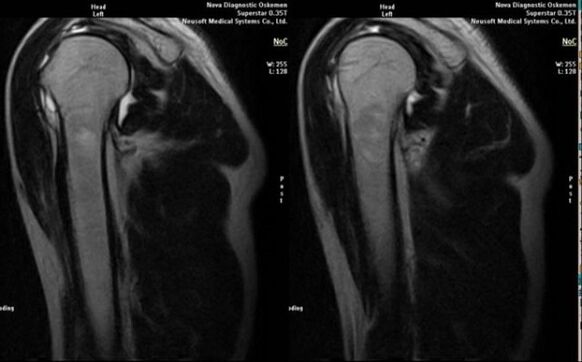

Glavna diagnostična metoda za odkrivanje deformirajočega osteoartritisa ramenskega sklepa je preprosta radiografija.

- magnetna resonanca in računalniška tomografija;

Znaki, ki neposredno kažejo na razvoj artroze, vključujejo pojav znatne zožitve sklepne špranje, sklerozo subhrustančnih struktur, tanjšanje same plasti hondrocitov, pojav osteofitov in odlaganje kristalov soli v intraartikularni tekočini.